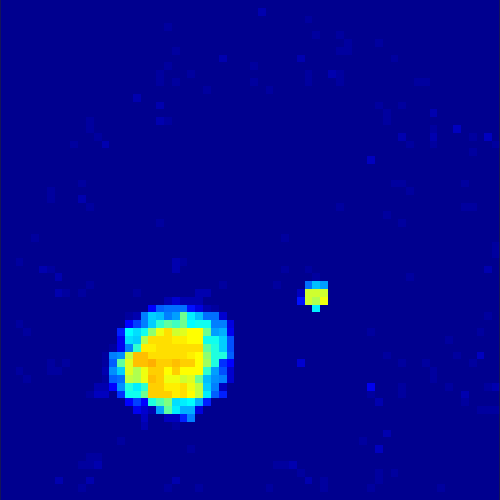

5.2 Monte Carlo Simulation

In order to test the behaviour of the proposed method in a more realistic, random-based test case, we performed a Monte Carlo simulation for dynamic SPECT imaging. First, we created a simple image phantom consisting of an outer and two inner circles which represents the structure of the region of interest (see figure 8(a)). Within those regions we assumed concentration curves over a time period of 90 time steps as displayed in figure 8(b). Based on the tracer intensity in an image frame at each time step, we created a variable number of random decay events (where the number is proportional to the average concentration in one pixel in the whole image frame per time step) with a probability proportional to the concentration in every subregion. They are detected by a virtual double head gamma camera rotating around the patient by 46 degrees per time step, which consists of 374 detector bins. Every simulated decay event is projected onto the scanner and counted by the corresponding detector bin.

In two different tests we fixed the number of events counted by the detector equal to (resp. ) times the average concentration in one pixel. The resulting sinogram images of the accumulated counts in each bin are shown in figure 9.

Based on the sinogram data we applied the proposed algorithm in order to reconstruct the original image sequence. The results for both test cases are shown in figure 10.

As one can see, the method is able to reconstruct the regions properly, even in case of a low count number. Within a number of iterations (average of 100 outer and 10000 inner iterations), the algorithm presents a reasonable reconstruction of the region of interest and the corresponding regional tracer concentration curves. Here, the parameters were not optimized as in the case of the synthesized data sets in the previous section, but kept fixed as , and . With futher optimized parameter values one could possibly provide even better results.